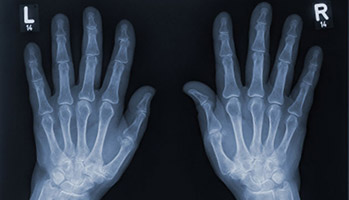

Arthrose : comment les patients gèrent-ils la douleur ?

L’Inserm, via le réseau ROAD to 2030, mobilise une communauté scientifique engagée dans la compréhension et le traitement des maladies ostéoarticulaires. Les résultats de l’enquête sur la douleur arthrosique viennent d’être publiés : moins d’une personne sur cinq a eu recours à l’éducation thérapeutique du patient pour apprendre à vivre avec une maladie chronique.